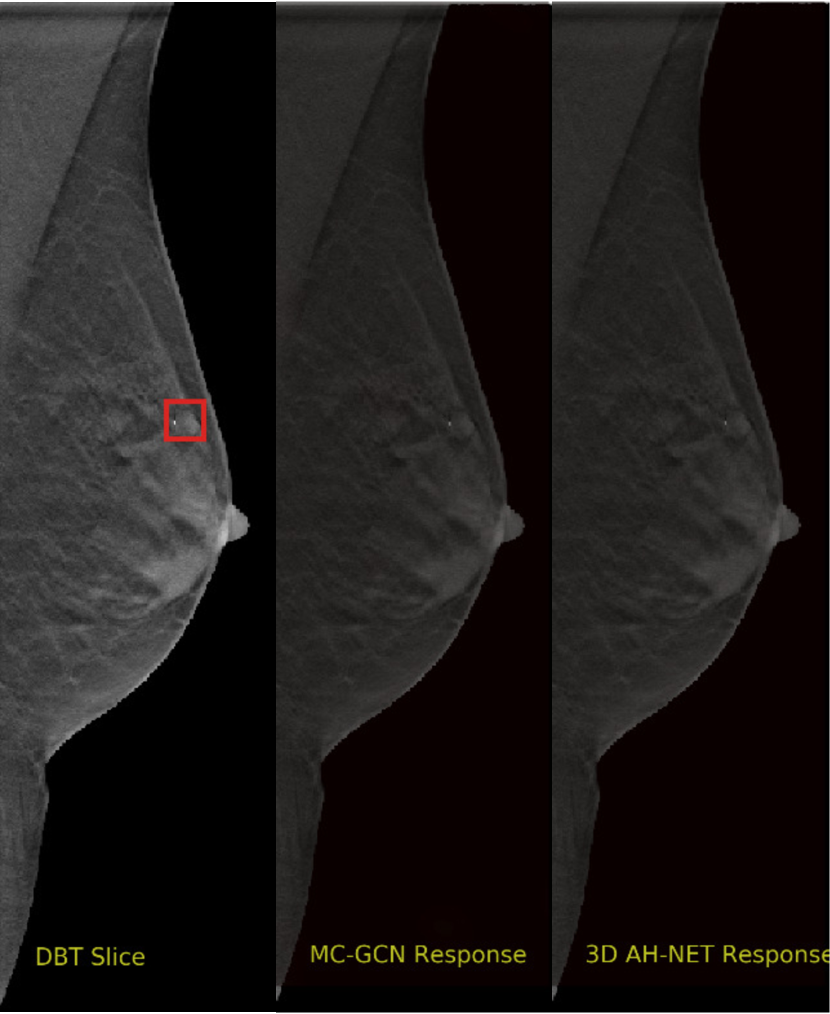

We selected some example slices from the DBT dataset to demonstrate the advantage of our proposed AH-Net for the Breast cancer screening. From Fig. 8 to Fig. 12, we show slices from five test DBT volumes that both the MC-GCN and the proposed 3D AH-Net could successfully detect the suspected breast lesion. The original DBT slice is shown on the left with the lesion annotated by our radiologist. Please note the original annotation is a 3D box. The figures in the middle and on the right are response maps from MC-GCN and 3D AH-Net overlaid on the original image, respectively. The detection locations obtained with non-maximal suppression are displayed with cross markers. As shown in the images, the proposed network can detect breast lesions varying in sizes and appearances. The confidence of the 3D AH-Net is usually higher than that of MC-GCN. From Fig. 13 to Fig. 17, we show five volumes that MC-GCN failed to detect the lesions since the lesions were not distinguishable from other breast tissues using the information within the slice. In contrast, 3D AH-Net was able to detect the lesions from such volumes using the 3D context between slices. As shown in Fig. 18 to Fig. 22, there are also volumes with lesions that both network failed to detect. Such lesions normally reside in the dense breast tissues. The boundary between these lesions and the normal breast tissues usually have low contrast. The networks sometimes also confuse them with other roundish structures in the breast such as lymph nodes or skin moles.

Figure 15: Example DBT slice 8 with a lesion that can only be detected by 3D AH-Net. The lesion is small and hard to be distinguished from other breast tissues. The lesion can be detected by considering the consistency of the structure across a few neighbouring slices.

Refer to caption